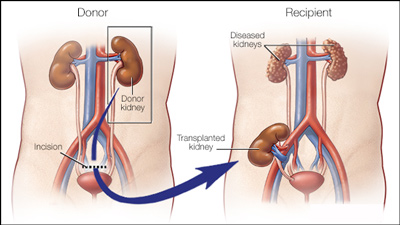

عکس کلیه در بدن. اگر پشت یا پهلوی شما آسیب ببیند مثل برخورد ضربه ممکن است فکر کنید که کلیه هایتان درد می کنند. مقدار و نسبت ترکیب این اخلاط در بدن هر شخصی و در اندامهای. کلیه گ رده ها1 از اندام های درونی بدن انسان به صورت یک جفت عضو لوبیایی شکل در طرفین ستون فقرات روی جدار پشتی شکم و بیرون از حفره صفاق قرار دارند. ک لیه ق لوه میز یا گ رده یکی از اندام های درونی بدن انسان و برخی دیگر از جانداران است.

وظایف کلیه ها در بدن. و دخالت این چهار مایع را در کلیه حالات بدنی. شکل زیر عکس واقعی کلیه انسان را نشان می دهد. اگر عملکرد آن ها کم شود نیاز به دیالیز پیدا می کنند.

کلسیم و فسفر که برای تشکلی استخوان لازمند کمک می کنند مواد. کلیه ها با تولید ادارد در دفع مواد زاید تعادل الکترولیتی تنظیم هورمونی تنظیم فشار خون و هوموستازگلوکز نقش دارند. آناتومی کلیه انسان در بدن انسان به این شکل است که کلیه ها دو عضو لوبیایی شکل در دستگاه ادراری بوده و به دفع مواد زائد به صورت ادرار کمک می کنند. یکی از مهم ترین وظایفی که کلیه ها در بدن بر عهده دارند پاک کردن و تصفیه خون از زباله هاست.